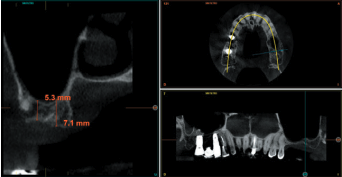

Todos los pacientes fueron tratados por un mismo cirujano, para la realización de la inserción de los implantes y la técnica de elevación transcrestal. Antes de la inserción de los implantes se utilizó una premedicación antibiótica consistente en amoxicilina 2gr vía oral una hora antes de la intervención y paracetamol 1 gramo vía oral (como analgésico). Posteriormente los pacientes prosiguieron con un tratamiento de amoxicilina 500-750 mg vía oral cada 8 horas (según peso) durante 5 días. Todos los pacientes fueron estudiados antes de la inserción de los implantes mediante modelos diagnósticos, exploración intraoral y realización de una tomografía computerizada de haz cónico (CBCT), analizado posteriormente mediante un software específico (BTI-Scan III). La cirugía se lleva a cabo mediante la técnica de fresado biológico descrita por nuestro grupo de estudio previamente, a bajas revoluciones, sin irrigación10, hasta ser finalmente completada mediante la elevación transcrestal con las fresas de corte frontal que se emplean también a bajas revoluciones. Una vez la membrana es accesible mediante la perforación crestal se despega mediante una ligera presión y se inserta el implante con el motor quirúrgico fijado a 25 Ncm y 25 rpm finalizando la inserción del implante con la llave dinamométrica. Todo el hueso recogido con las fresas se conserva en PRGF-Endoret fracción 2 sin activar, para posteriormente ser utilizado como injerto óseo particulado en la elevación, sin otros materiales accesorios9,12. Una vez finalizada la cirugía se realiza una radiografía periapical con paralelizador que será la que se utilice como punto de partida. Los pacientes acuden posteriormente para la realización de radiografías periapicales de control, tomadas con la misma técnica y sobre estas radiografías se realizan las mediciones necesarias para comprobar la estabilidad y pérdida ósea crestal de los implantes. La medición de la pérdida ósea marginal se realizó en la última radiografía periapical realizada con posicionador de seguimiento.

En la Figura 2 se muestran los diámetros y longitudes de los implantes incluidos en el estudio en función de los milímetros de cresta ósea residual en altura. La densitometría media de la zona de inserción del implante del grupo fue de 293,33 HU (+/- 144,99). El torque medio de los implantes estudiados fue de 27,33 Ncm (+/- 16,99). Todos los implantes se cargaron en dos fases quirúrgicas y en todos se llevó a cabo una elevación de seno transcrestal con injerto óseo autólogo particulado obtenido del fresado, embebido en PRGF-Endoret como marterial de injerto. En ninguno de los casos se registraron complicaciones relativas a la cirugía. Los implantes presentaron un seguimiento medio de 13,33 meses tras la carga (+/- 3,09), no encontrándose complicaciones ni fracasos durante este tiempo de seguimiento, por lo que la supervivencia fue del 100%. Todos los implantes fueron rehabilitados mediante prótesis múltiple atornillada mediante elemento intermedio (transepitelial múltiple, Multi-im®), encontrándose dos de los implantes ferulizados a otros de la misma longitud (4,5 mm) y el resto a longitudes mayores. La ratio corona-implante medio para el grupo de estudio fue de 2,43 mm (+/-0,45). La pérdida ósea mesial final media de todos los implantes fue de 0,42 mm (+/- 0,51) y la pérdida ósea distal final media de 0,16 mm (+/-0,34). En las Figuras 3 –13 se muestra uno de los casos incluidos en el estudio.